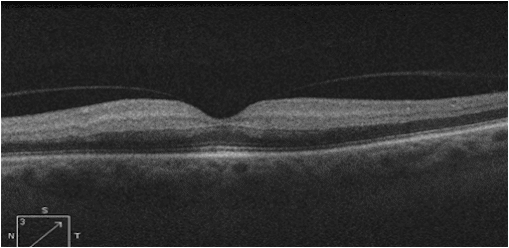

What are the 3 things wrong with this OCT?

(click on image for answer)